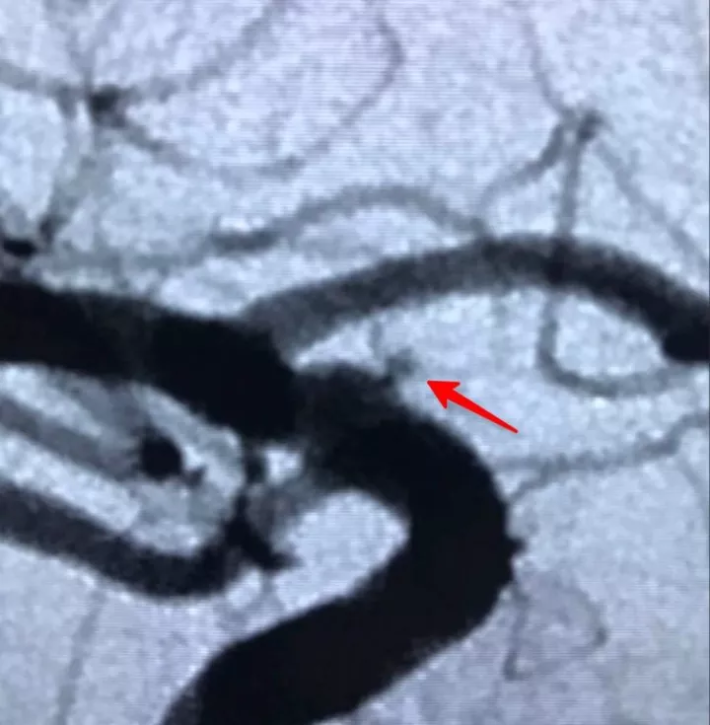

瘤太小了,放大看(箭头所指)